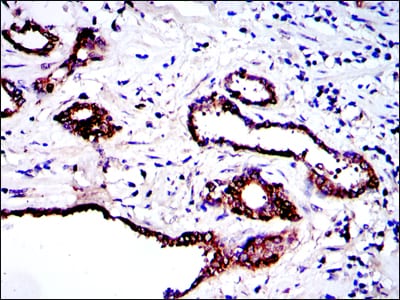

| IHC | 1/200 - 1/1000 | Human,Mouse,Rat |

PRK2 antibodies are essential for investigating its expression, localization, and activation in various tissues and disease contexts. Dysregulation of PRK2 has been implicated in cancer, neurodegenerative disorders, and cardiovascular diseases. For instance, elevated PRK2 levels correlate with tumor progression and metastasis in certain cancers. Researchers utilize PRK2 antibodies in techniques like Western blotting, immunohistochemistry (IHC), and immunofluorescence (IF) to explore its functional mechanisms or diagnostic potential.